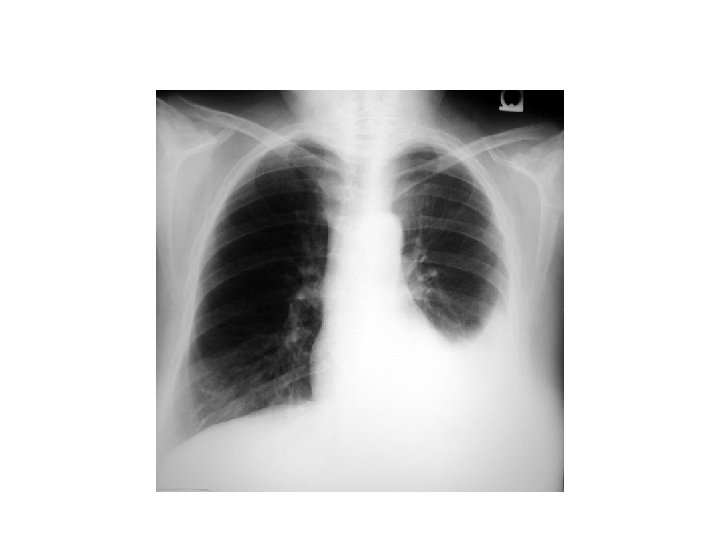

• Quelques mois plus tard : AEG, douleur basithotacique droite, dyspnée • Épanchement pleural droit 3/4 de l’hémichamp

Que faites-vous? • Ponction pleurale exploratrice : – Biochimie (ac hyaluronique) – Cytologie/ana-path • Biopsie pleurale? • Thoracoscopie – Diagnostic – « Traitement »

Cas clinique

Quel diagnostic suspectez vous? Mésothéliome